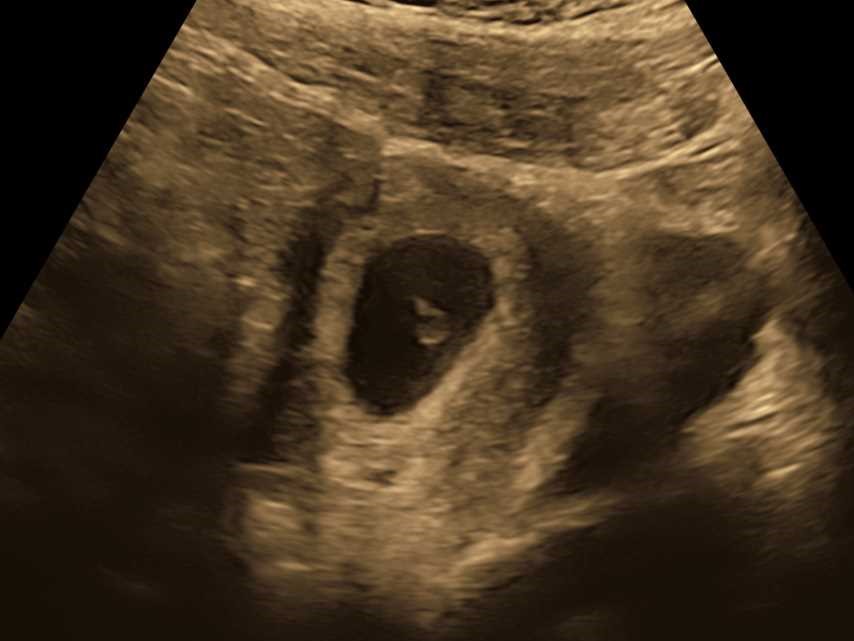

Ultrasound was booked in for Tuesday, which was week 7, day 2, so very early days. Technically a dating ultrasound, but given we knew the conception date, this was to measure and make sure everything was looking good.

I got to see a tiny dot, I guess. There wasn’t much to it. But it was there. I didn’t get to hear a heartbeat, too early for that, but we got to see it, and they could measure it – 146 beats per minute, very good heartrate. And the CRL (which I have just learnt is the “Crown to Rump” measurement) was 1.10cm. Tiny! But it was something.

I know it was still early days, and anything could happen at this stage, but to know there was something there was very cool. And to get some photos for my records.